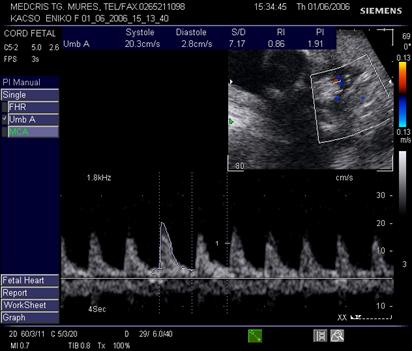

Doppler in circulatia cerebrala

Creierul fetal primeste circa 40% din debitul cardiac total. Cele 3 scurtcircuite ale aparatului fetal cardio-vascular: canalul arterial, ductul venos si foramen ovale, permit devierea sangelui bine oxigenat spre creier, cord si suprarenale, in caz de hipoxie (teritorii privilegiate).

Daca cresterea tensiunii arteriale si a frecventei cardiace din cadrul hipoxiei fetale, sunt consumatoare mari de oxigen si autolimitate, redistribuirea fluxului de sange se face prin vasodilatatie compensatorie in "teritoriile privilegiate."

Poligonul Willis, sediul anastomozelor vasculare din principalele vase cerebrale, se identifica plecand de la sectiunea transversala a masurarii diametrului biparietal, prin baleierea sondei spre sectiunea bazei craniului.

Artera cerebrala medie are directia inainte si in afara, primeste sange din carotide si arterele vertebrale. Planul de reperare este cel al pedunculilor cerebrali, lateral de poligonul Willis. Ea reprezinta sediul preferat pentru velocimetria cerebrala.

In sarcina normala, rezistenta crescuta cerebrala se traduce in velocimetria cerebrala prin diastola scazuta. Aspectul normal al velocimetriei cerebrale permite aprecierea unei stari de bine fetale pentru 2 saptamani [17].

In cazul unei patologii gestationale (HTA, RCIU) repetarea examenului se va face la 2 saptamani, iar pentru valori anormale la 24 - 72 ore.

Velocimetria cerebrala , singura, nu aduce informatii asupra hipoxiei din circulatie.

Indicele Arbeille (raport cerebro-placentar) = IR a. cerebrala medie/IR a. ombilicala este supraunitar in conditii de sarcina fiziologica.

In afara fenomenelor de redistribuire a fluxurilor vasculare fetale, amplitudinea vitezelor diastolice la arterele cerebrale ramane inferioara fata de artera ombilicala, deci valoarea indicelui cerebroplacentar este supraunitara. Vasodilatatia cerebrala din redistribuirea fluxurilor sanguine, din suferinta fetala cronica, va determina o scadere semnificativa a IR cerebrala, cu trecerea indicelui cerebroplacentar in valoare subunitara.

Fig. nr.325. Doppler normal pe a. cerebrala medie , la 27 sapt.

Fig. nr. 326. Doppler pe artera cerebrala medie cu diastola crescuta si inversarea indicilor de rezistenta ( indicele Arbeille subunitar ) la fat de 34 sapt cu retard major de crestere intrauterina si sdr genetic